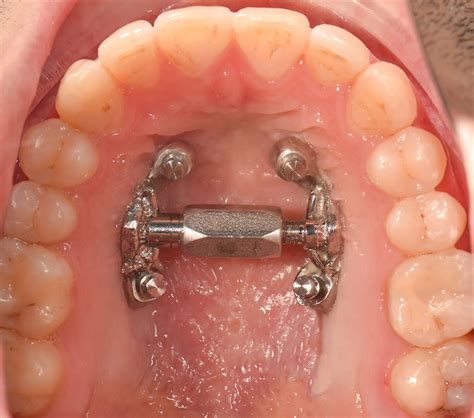

Disyuntor utilizado en la Expansión Rápida del Maxilar (ERM).

Este tratamiento pretende aumentar la distancia transversal por separación de ambas hemiarcadas a nivel de la sutura media del paladar, utilizando un aparato expansor fijo y rígido, que se activa diariamente aproximadamente medio milímetro y que aumenta la base apical y el espacio disponible para las piezas dentarias permanentes.

Los disyuntores más utilizados son los expansores de tipo Hass, Hyrax y de McNamara o adhesión directa. El expansor de Hyrax y Hass se utilizan en denticiones mixtas o permanentes tempranas, compuestos por bandas cementadas a los molares y alambres que recorren las caras palatinas de los ectores laterales.

El expansor tiene un tornillo con un orificio, y se utiliza una llave especial para girarlo. Por lo general, indico que se gire la llave una vez al día (a veces en días alternos, según el caso). Cada giro es muy pequeño (un cuarto de vuelta) y genera una leve presión en los huesos del paladar.

Al activar el tornillo diariamente, el paladar se va ensanchando milímetro a milímetro. Este proceso se denomina disyunción palatina. Lo maravilloso es que el organismo del niño responde generando nuevo hueso en el espacio que vamos abriendo en la sutura.